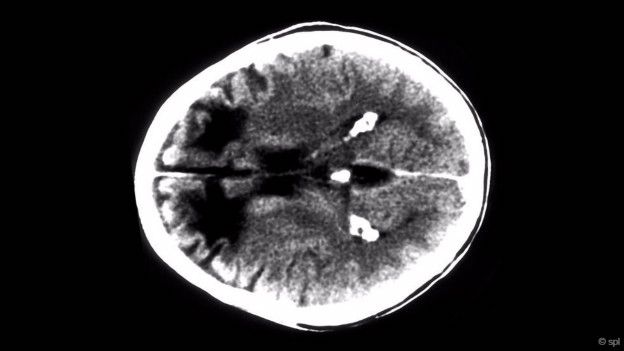

Bir zamanlar ruhsal bozukluğu olan kişilere uygulanan bu işlemle, kafatasında açılan küçük bir delikten, beyindeki ön loblarla beynin diğer kısımları arasındaki sinir bağlantılarının kesilerek duygusal tepkilerin önlenmesi hedefleniyordu. 2011’e kadar devlet sırrı olarak saklanan bu bilgi, Nijensohn’un Eva Peron’un ölümünün ardından yapılan kafatası röntgenlerini ele geçirmesiyle sır olmaktan çıkmıştı. Nijensohn, Peron’un kafatasında delik açılmış olduğuna dair veriler olduğunu söylüyordu.